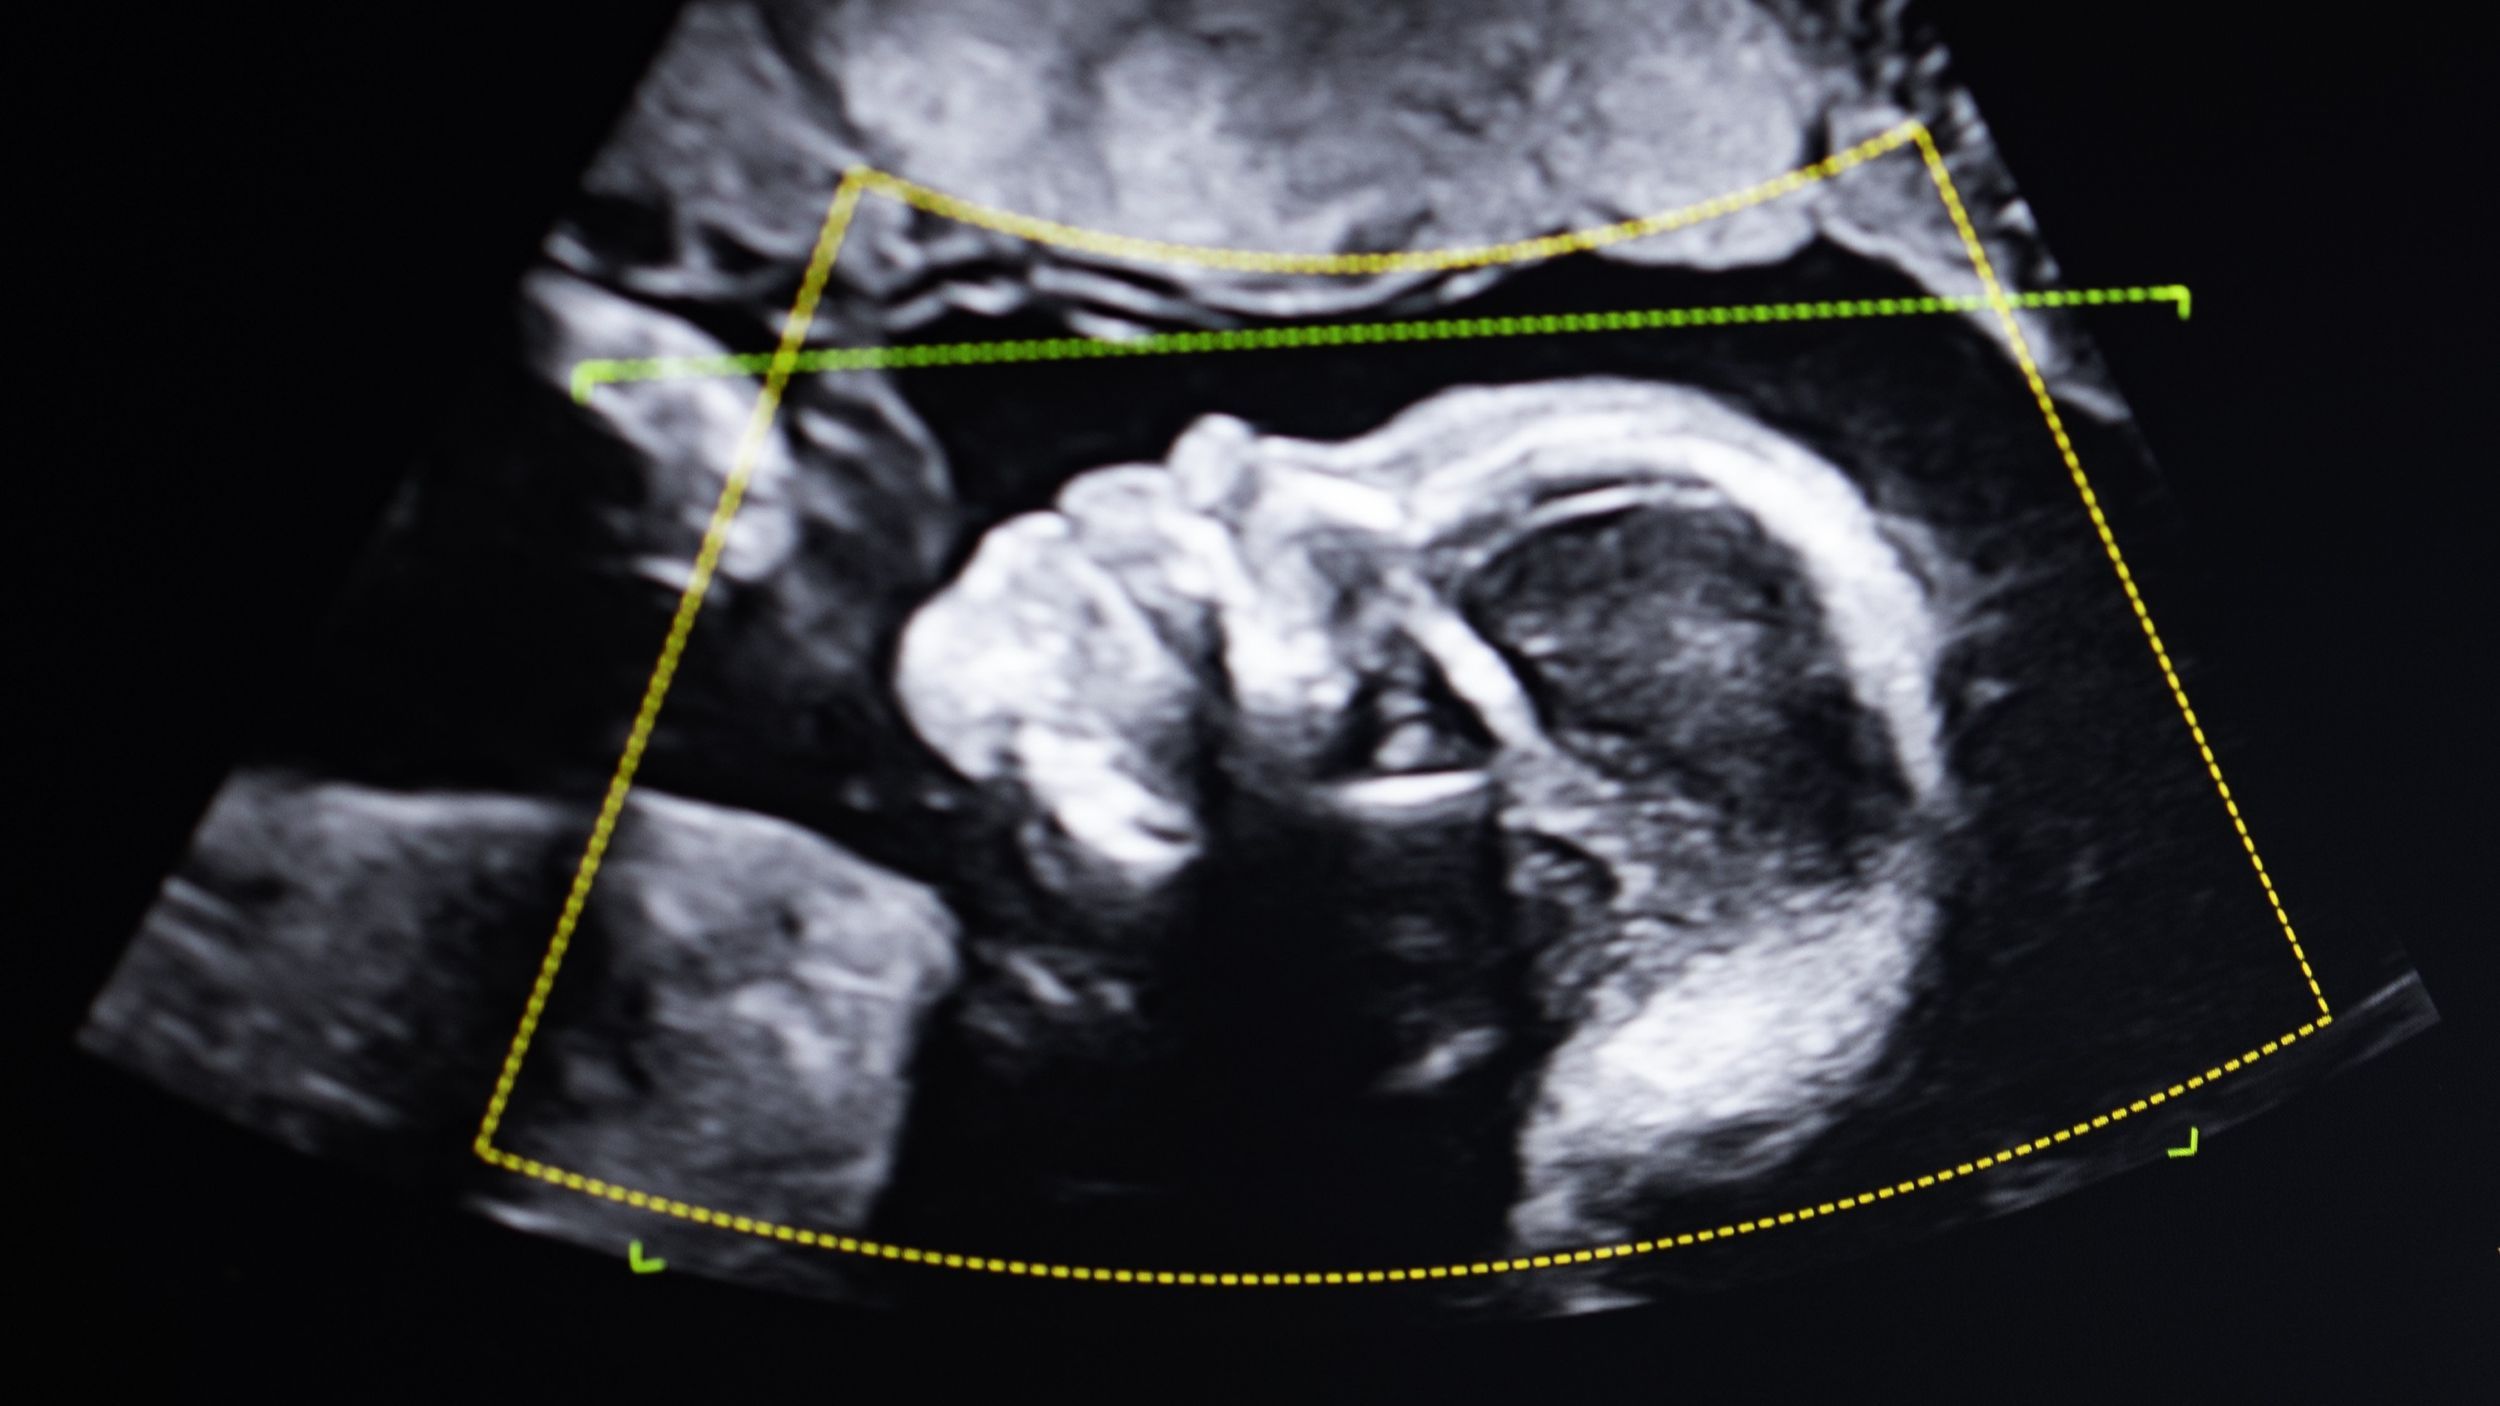

Delia Atenea never considered going under the knife — she’d always been slender, fit and confident in her own skin. But three pregnancies, including two…